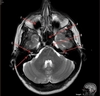

Image weighting and axis

T2 Axial

A

Caudate Nucleus

B

Thalamus

C

Third ventricle

D

Lentiform Nucleus

E

Frontal Sinus